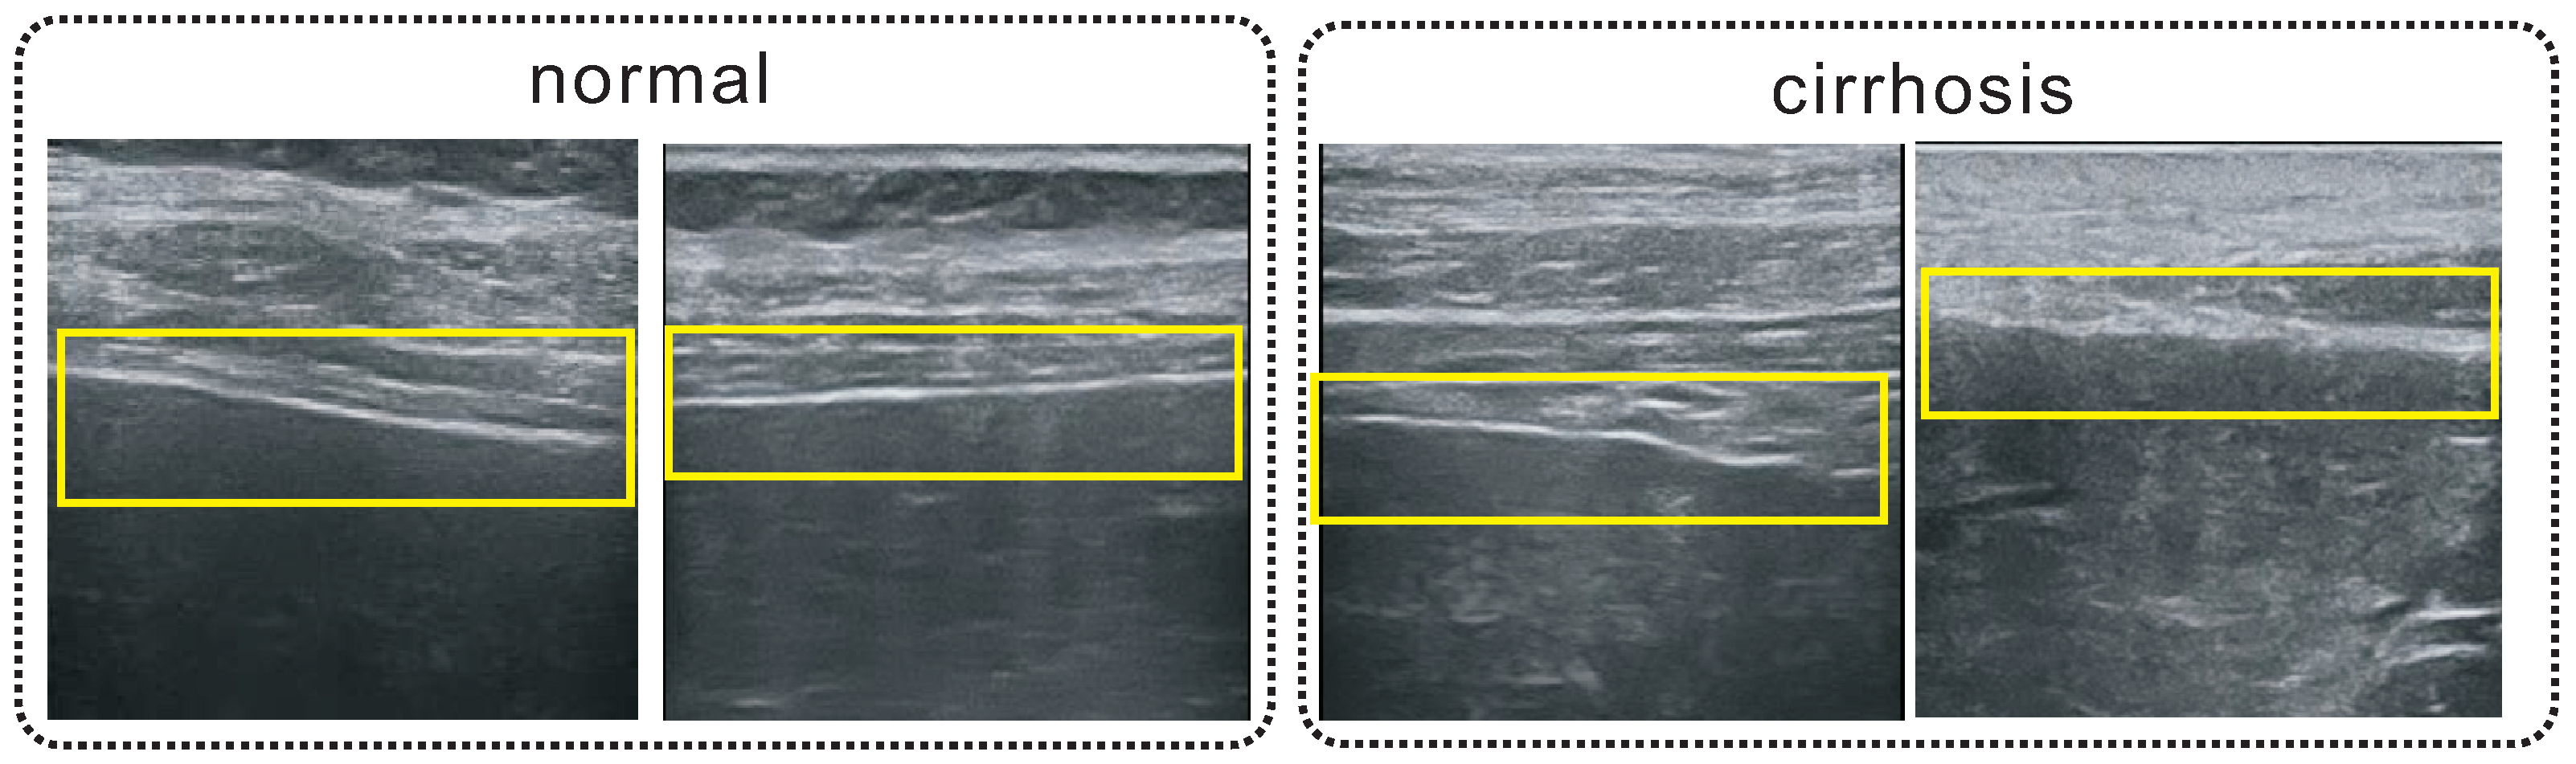

3. Liver Capsule Detection

5.1. Performance of the Detector